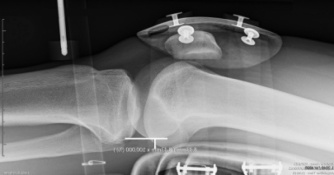

Knee radiography picture

Radiography is also a recognized technique for analyzing the anterior cruciate ligament. The TELOS is a famous device, which was used to run radiography assessment on patients suffering from ACL injuries by analyzing the position of the tibia compared to the femur while applying a single force on the tibia.

The objective results provided by this type of evaluation are interesting but the radiography technology, which is required, makes it very invasive for the patient thus the reason it holds the 4th position.